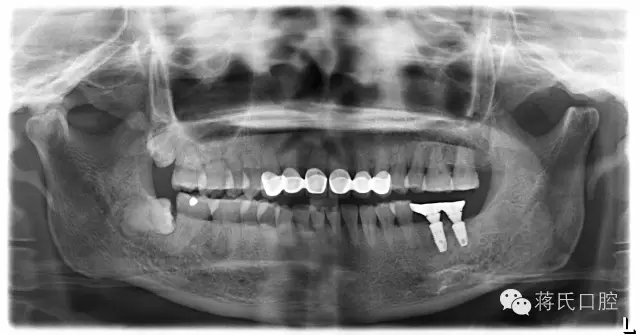

6.修復(fù)后全景片